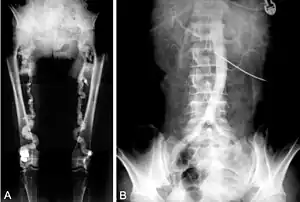

![]() B. Translumbar aortography shows near-total obstruction of the femoral arteries in a patient with Monckeberg's arteriosclerosis. | |